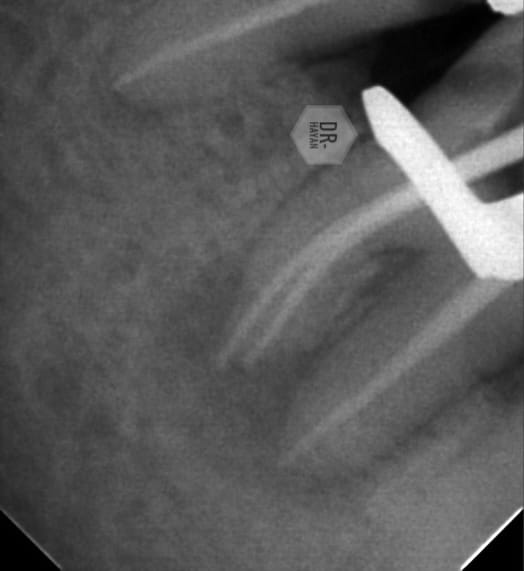

Master cone

30/4 mb , ml

25/6 of D one

Cold hydraulic obturation by bio ceramic sealer

With lateral canal in destal root